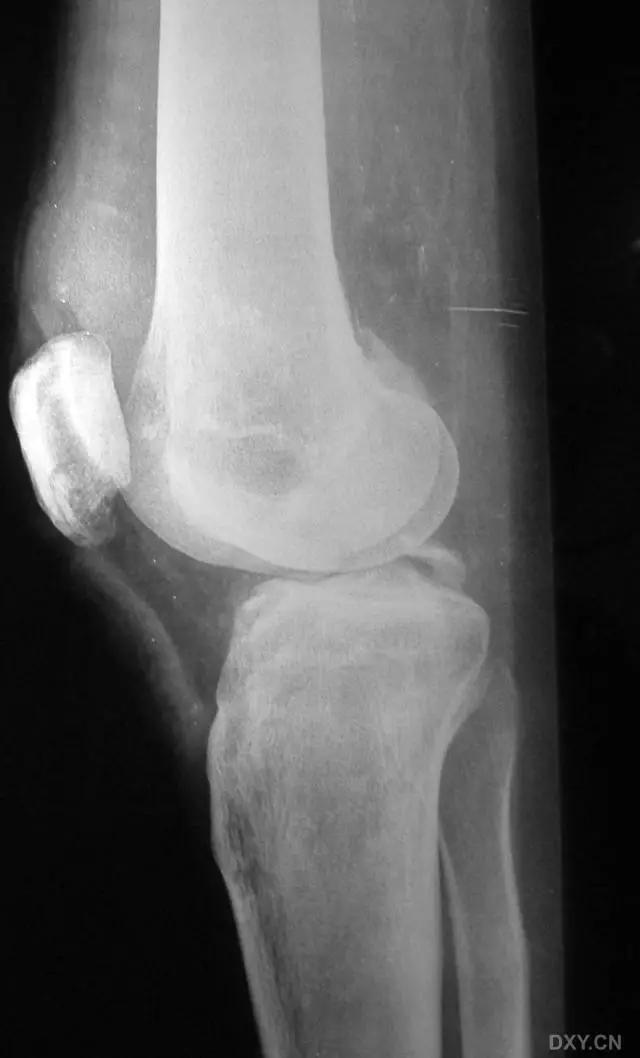

8. Segond 骨折和反向 Segond 骨折

(1)Segond 骨折

是发生在胫骨平台外侧的垂直撕脱性骨折。这种骨折在前后位 X 线片上显示最佳。屈曲位时膝关节受到内旋*力暴**作用,导致皮质骨撕脱性骨折,这种骨折常发生在运动员身上。

常引起股骨内髁和胫骨平台后内侧骨挫伤,75%~100% 的患者伴前交叉韧带断裂,33% 的患者伴外侧半月板损伤。

一位足球运动员的 Segond 骨折。A 正位片示关节线下方胫骨外侧皮质撕脱(箭头)。B MRI 冠状位 T1 加权像示附着于髂胫带的骨折碎片(空箭头)(来源:Radiol Clin N Am 53 (2015) 737–755,YU,Ohio)